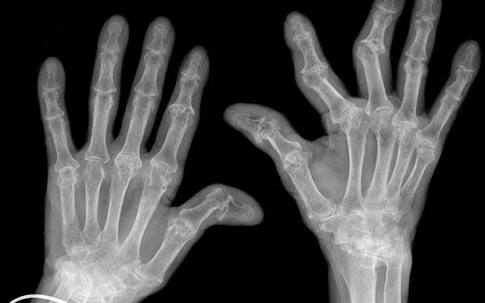

类风湿关节炎,其主要的病理基础是滑膜的改变,当滑膜出现了类风湿滑膜炎改变以后,会逐渐的破坏掉关节腔内的软骨,导致关节间隙的狭窄和关节的粘连,严重的影响患者的生活质量,很多人因为手部的变形甚至筷子都拿不了。

当然当很多患者已经到了晚期,关节已经出现了明显的变形,从相关的查体以及x光片子,也可以明确患者是否存在类风湿性的关节炎。从下图您仔细看就会看出正常的手与类风湿性关节炎手部的骨骼改变。

另外类风湿这种疾病也会导致患者出现比较严重的骨质疏松,建议类风湿患者一定要做双能x线检查,明确自己是否存在骨质疏松,或者说骨质疏松到了什么样的程度,根据结果进行系统的抗骨质疏松治疗。